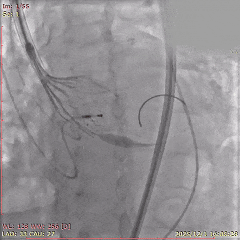

术中影像

初始造影确定无冠窦

瓣膜瓣下定位释放,全展开后位置良好

左侧位造影,瓣膜位置可,选择脱钩

脱钩后造影,瓣膜位置可,无反流